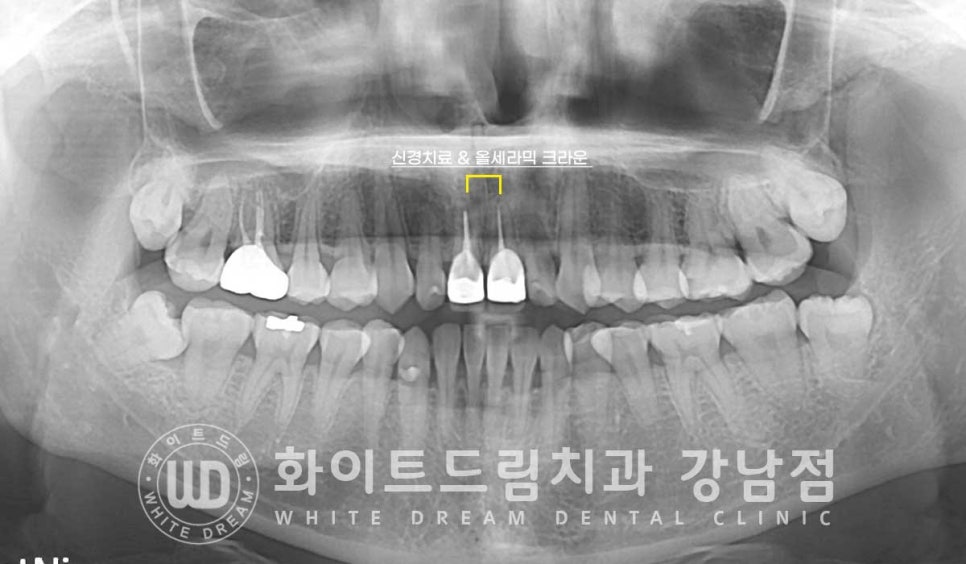

환자분은 앞니 11, 21번 치아 두 개가 올 세라믹으로 치료가 되어 있는 상태였는데

크라운 자체에 문제는 없지만 크라운 교체와 전치부 라미네이트 치료를 동반하여

전체적으로 치아 색을 톤 업(tone-up)을 원하기로 치료 계획을 세웠습니다.